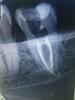

Miss Doc Опубликовано 30 октября, 2012 Поделиться Опубликовано 30 октября, 2012 Вот хоть тресни,не смогла найти хотя бы третий,не говоря уж о четвертом,причем тот,который не небный вообще как бы посередине между предполагаемыми щ-м и щ-д каналами. на снимке корень с этим каналом параллельно небному идет,других корней не вижу. Положила кальций, в след раз поковыряюсь еще,но вот интересно, может быть 2 канала? Ссылка на комментарий

ger_berra Опубликовано 30 октября, 2012 Поделиться Опубликовано 30 октября, 2012 Вот хоть тресни,не смогла найти хотя бы третий,не говоря уж о четвертом,причем тот,который не небный вообще как бы посередине между предполагаемыми щ-м и щ-д каналами. на снимке корень с этим каналом параллельно небному идет,других корней не вижу. Положила кальций, в след раз поковыряюсь еще,но вот интересно, может быть 2 канала? Все 3 или 4 могут находиться на одной прямой. Ссылка на комментарий

Ico Опубликовано 31 октября, 2012 Поделиться Опубликовано 31 октября, 2012 Может поможет!В моем случае пришлось сильно засверлить устье.В одном случае нашел,в другом нет.Небныи и дистальныи на однои линии 2-3 мм друг от друга. Ссылка на комментарий

Miss Doc Опубликовано 31 октября, 2012 Автор Поделиться Опубликовано 31 октября, 2012 (изменено) Может поможет!В моем случае пришлось сильно засверлить устье.В одном случае нашел,в другом нет.Небныи и дистальныи на однои линии 2-3 мм друг от друга. Сегодня пришел ко мне мой пациент(позвонил,сказала,что времяшка выпала,оказалось просто скололась сверху),ну,думаю,как раз час у меня есть свободный,покопаюсь еще. Сделала анестезию(пациент без нее боиццо=)),начала пилить,допилила до того, что почти сделала дырку(надеялась,что это устье дистального),оказалось не устье..закрыла триоксидентом Пыталась и на одной линии искать между щечным и небным,но там никаких дорожек даже нет.. Изменено 31 октября, 2012 пользователем Miss Doc Ссылка на комментарий